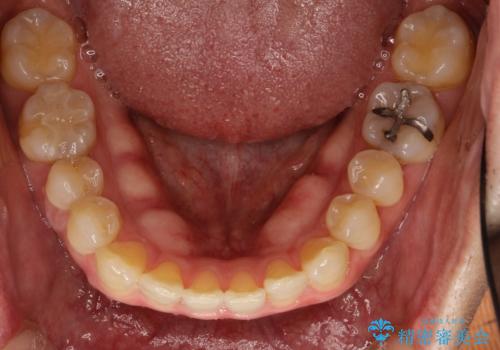

- 上顎の正中の隙間が気になるとのことで来院されました。

下の歯と歯の間をわずかに削り、スペースを作り、正中の隙間を閉じる計画としました。

装置はインビザラインにて行いました。